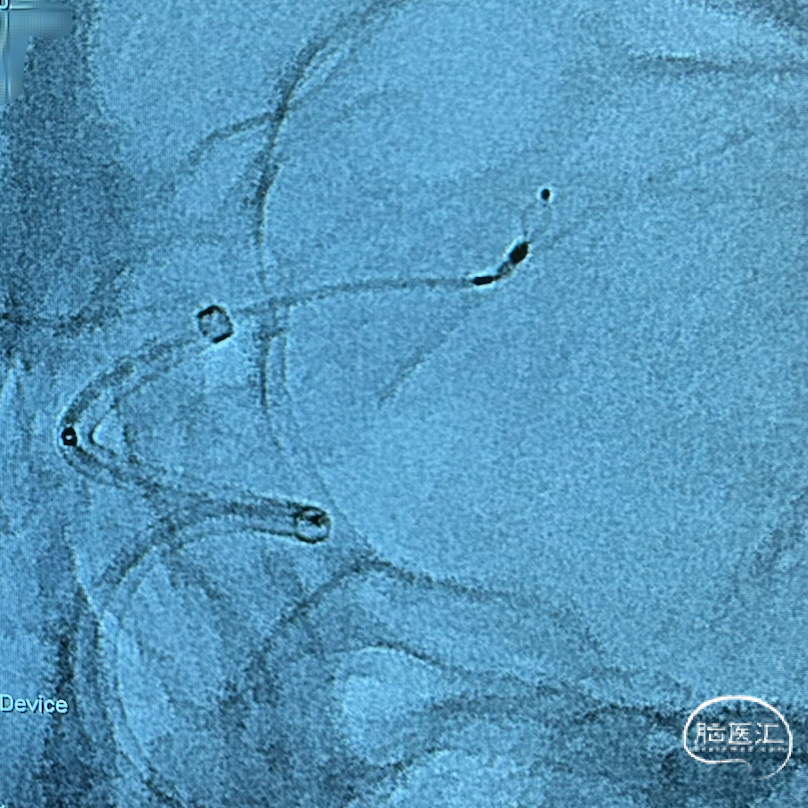

首先将Synchro 2 微导丝导引单弯塑形后的VIA™ 17微导管超选至左侧大脑中动脉主干远端,进一步上高5F 115cm中间导管至左侧颈内动脉末端。

回撤微导丝及微导管,操控微导丝将VIA™ 17微导管超选入动脉瘤

调整微导管张力,送入4mm*2mm WEB™,从“萌芽”逐步过渡到“开花”。

因动脉瘤载瘤动脉与大脑中动脉主干存在成角,在输送WEB™过程中蓄积了一定成角的张力,当输送WEB™至其解脱点与微导管远端标记点重叠时,WEB™尾端打开不理想,呈“葫芦”状。

部分收回WEB™,准备调整微导管张力后尝试再次释放。

轻柔“推-拉”调整系统张力,输送WEB™后成功打开。

微导管塑形与张力调节:由于载瘤动脉成角,微导管需预塑形为合适角度的单弯形态以顺应血管走行。中间导管虽跟进至颈内动脉末端,但微导管成角仍导致微导管头端张力蓄积,首次释放时WEB™尾端呈“葫芦状”未完全展开。此时需部分回收装置,调整微导管头端位置,通过轻柔“推-拉”技术释放张力,确保微导管与动脉瘤长轴同轴。

WEB™释放的实时评估:在成角部位,装置展开易受血流冲击影响。需通过多角度造影动态观察WEB™形态,重点确认瘤颈覆盖是否完全、尾端是否充分展开。本例通过反复调整,最终实现装置稳定贴壁,术后利用西门子自带多容积三维重建,分析扰流装置的位置,证实了技术操作的可靠性。